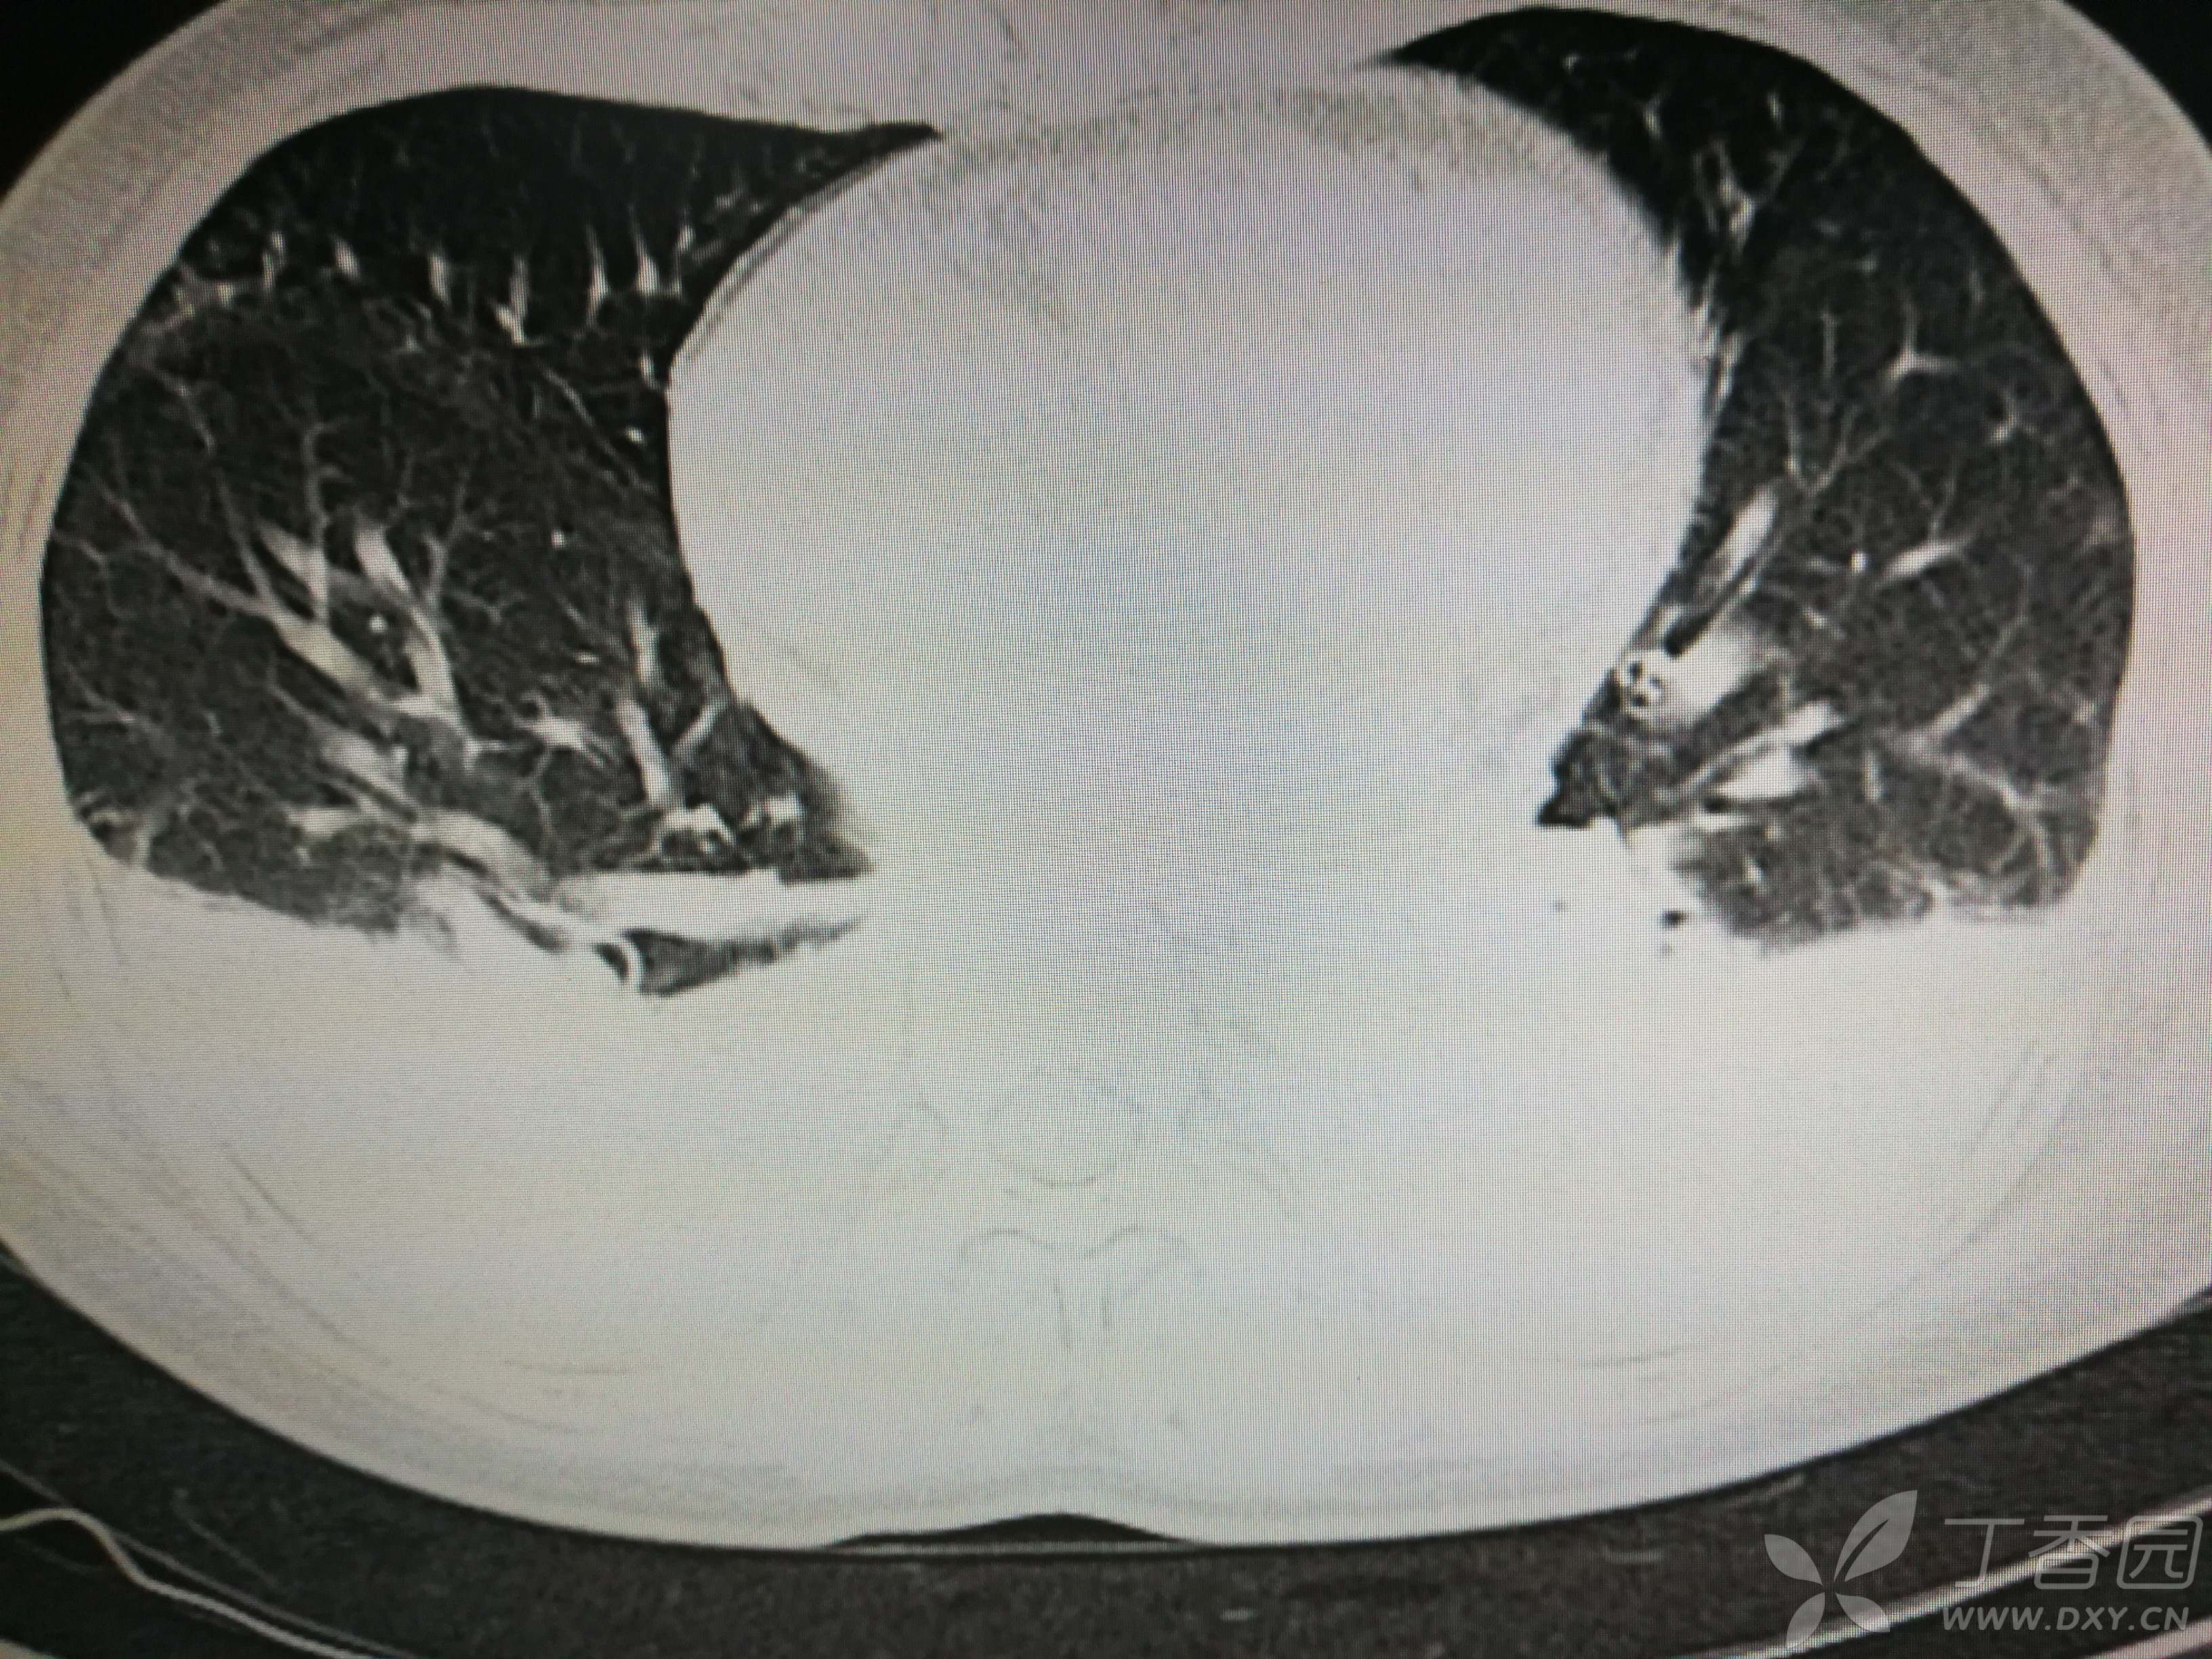

给予低分子肝素钙针抗凝、七叶皂苷钠针消肿及骨牵引固定等等治疗。入院后第四天行“左侧股骨下段骨折切开复位内固定术”(术前查双下肢彩超:双下肢深静脉血流通畅),手术顺利,术后予预防感染、预防血栓形成等治疗。术后患者无明显发热,生命体征平稳。术后第四天复查血常规:白细胞13.4×109/L,血红蛋白84g/L,血小板在正常范围。生化:白蛋白35.7g/L,余无明显异常。当天,患者开始出现轻度胸闷气急,可耐受。术后第五天患者胸闷气急加重,无胸痛,无背痛,无咯血,无意识障碍,无头晕头痛,无恶心呕吐等,急查凝血功能:纤维蛋白原降解产物12mg/L,D二聚体4000ug/L,余无明显异常。查动脉血气分析:pH7.52,氧分压62mmHg,二氧化碳分压30mmHg,碱剩余1.8mmol/L,乳酸1.0mm/L,血红蛋白86g/L。查胸部CT见下(先视频后图片):